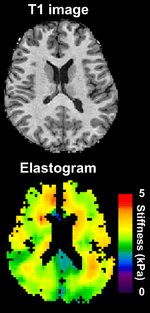

Magnetic Resonance Elastography (MRE)

Magnetic resonance elastography (MRE) [15] was introduced in the mid-1990s, and multiple clinical applications have been investigated. In MRE, a mechanical vibrator is used on the surface of the patient's body; this creates shear waves that travel into the patient's deeper tissues. An imaging acquisition sequence that measures the velocity of the waves is used, and this is used to infer the tissue's stiffness (the shear modulus).[16][17] The result of an MRE scan is a quantitative 3-D map of the tissue stiffness, as well as a conventional 3-D MRI image.

One strength of MRE is the resulting 3D elasticity map, which can cover an entire organ.[2] Because MRI is not limited by air or bone, it can access some tissues ultrasound cannot, notably the brain. It also has the advantage of being more uniform across operators and less dependent on operator skill than most methods of ultrasound elastography.

Because elastography does not have the same limitations as manual palpation, it is being investigated in some areas for which there is no history of diagnosis with manual palpation. For example, magnetic resonance elastography is capable of assessing the stiffness of the brain, and there is a growing body of scientific literature on elastography in healthy and diseased brains.